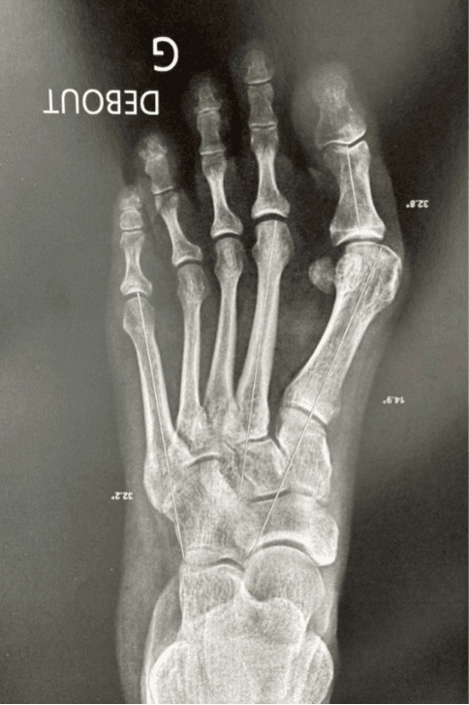

Radio avant l’intervention